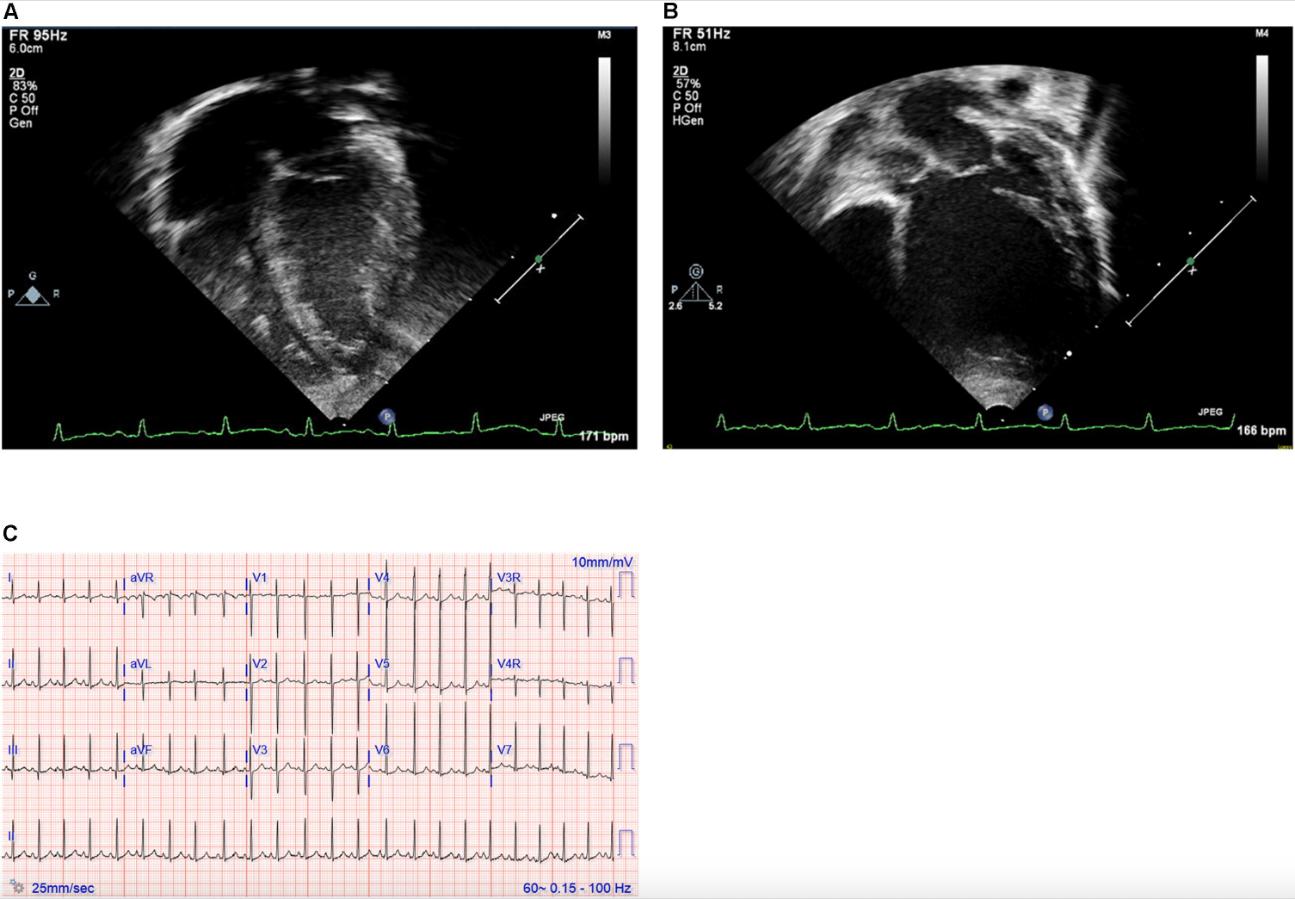

Figure 1. (A,B) Echocardiography images and (C) electrocardiogram. Still images obtained from echocardiogram of the proband at ages 2 weeks (A) and 12 months (B). Note particularly the progressive dilation and prominent rounding of the left ventricle (LV) in the later image. (C) Electrocardiogram at 19 months of age demonstrating sinus rhythm and left ventricular enlargement. |